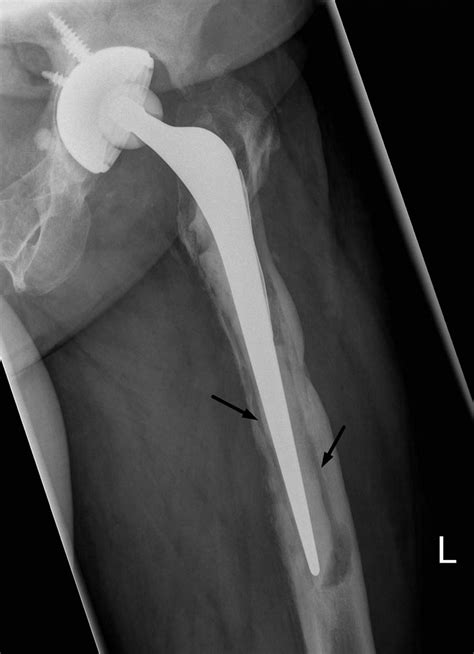

Follow Up After Total Joint Replacement | Proliance Orthopedic